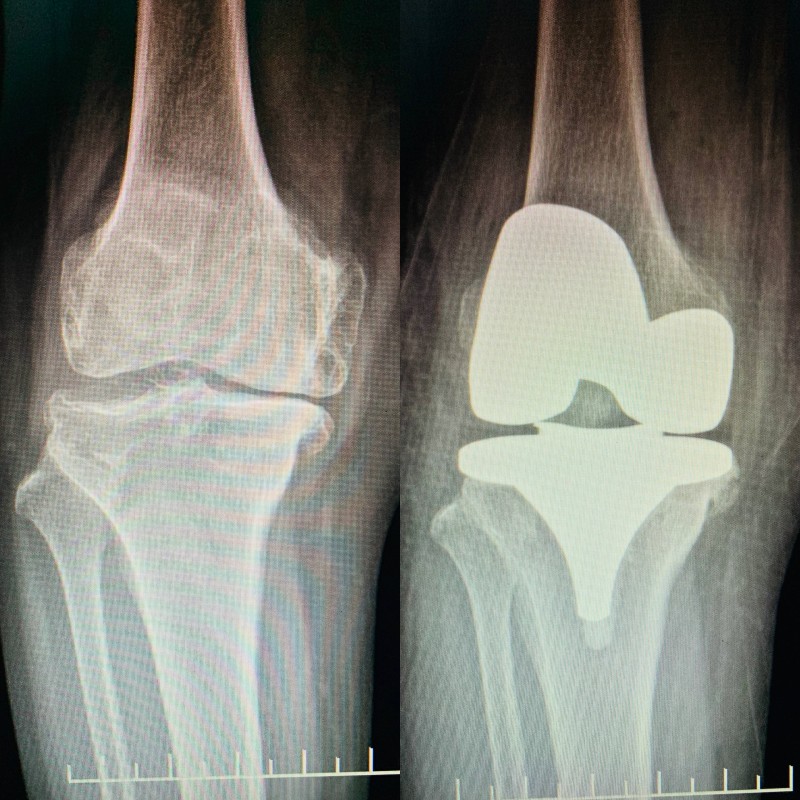

(膝關(guān)節(jié)置換術(shù)前術(shù)后對(duì)比)